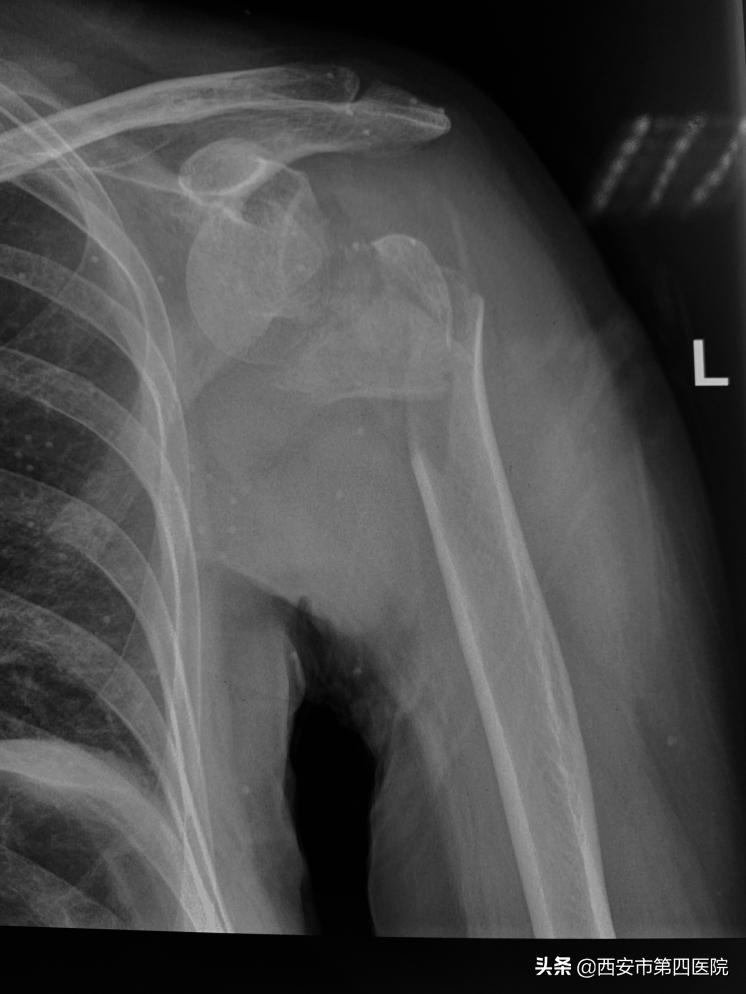

在医院领导及综合办公室的协助下,创伤组各级医生立即进行了组内讨论。赵大娘这一摔可真不得了,肱骨近段被摔成了四部分:也就是肱骨头、肱骨大结节、肱骨小结节及肱骨干,同时还合并有肱骨头的前脱位及喙突的骨折。

骨折示意图